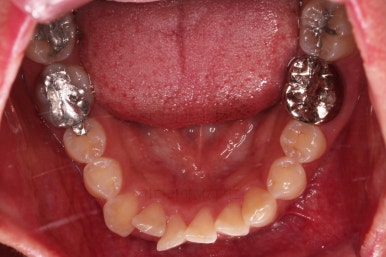

초진 시, 입 안의 모습이에요.

위아랫니가 삐뚤고 교합이 약간 맞지 않네요.

입 안만 보면 심플하게 교정하면 되겠다 싶지만, 문제는 다른 곳에 있었어요.